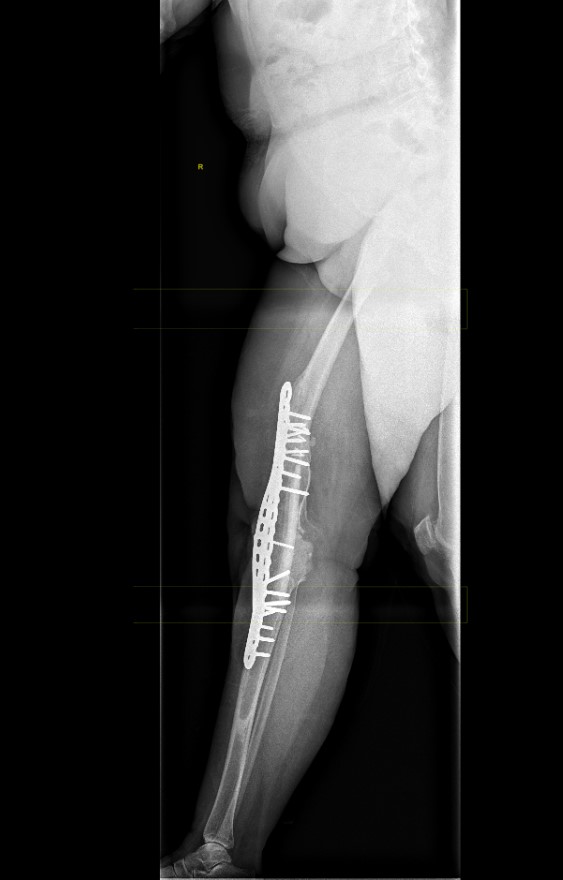

2. Double plating

Dual plates